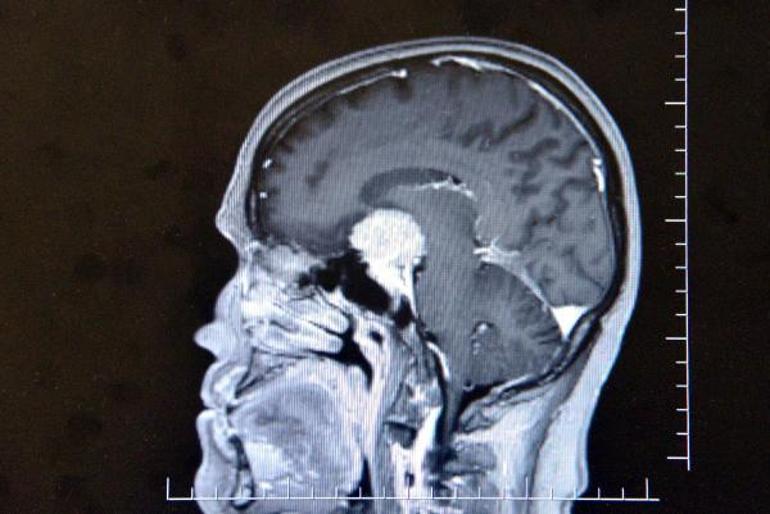

Altun tarafından yapılan muayene ve tetkiklerde Gül'ün beyninde ceviz büyüklüğünde tümör olduğu ve gözündeki sorunun tümörden kaynaklandığı tespit edildi. Altun, Ayşe Gül'e acilen ameliyat olması gerektiğini ancak tümörün ana şah damarlarının olduğu bölgede olmasından dolayı ölüm riskinin yüzde 80, yaşaması halinde ise felç kalma ihtimalinin de çok yüksek olduğunu söyledi. Tüm riskleri kabul eden Gül, Altun tarafından ameliyata alındı. Ameliyatı beyni açmak yerine endoskopik yöntemle gerçekleştiren Altun, tümörü Gül'ün burnundan çıkardı.

"Hastamız görme şikayetiyle ilgili birçok yere gitmiş ancak hastalıkla ilgili bir teşhis konulamamış. En son çekilen filminde ana şah damarlarını tamamen saran, görme sinirini tamamen kapatan, solunumla hayat merkezinin önünde geniş bir kitle olması üzerine hasta tarafıma geldi. Hastayı değerlendirdikten sonra endoskopik yöntemle kamera eşliğinde burundan girerek ceviz büyüklüğünde, 3,5 santim genişliğindeki kitleyi almaya karar verdik. Hastamız tüm riskleri kabul etti. Tabi burada önemli olan ana damarlar üzerinde geçmesi, ana damarlarını sarması, görme sinirinin üzerinde olması ve solunum merkezine doğru ilerlemesi bir risk faktörüydü. Biz bununla ilgili gerekli tedbirlerimizi aldıktan sonra ameliyata girdik. Ameliyatta başarılı bir şekilde gerçekleşti, herhangi bir görme sinirinde, ana damarlara veya solunum hayat merkezine dokunmadan tümörü tamamen burundan temizledik. Hastamız gayet iyi rahat. Beynin orta yerinde taban bölgesinde dediğimiz, 3,5 santim ebadında, ceviz büyüklüğündeki tümörümüz solunum hayat merkezinin önünü kaplaması ve oraya doğru ilerlemesi,sağ ana damarlara doğru ilerleyip tamamen içerine alması ve hipofiz bezini alttan yukarı doğru sarması, bu ebada ulaşması milyonda bir oranda gözükür. Biz bu tümörü, burundan girilerek endoskopik yöntemle tamamen ana damarlara herhangi bir zarar vermeden çıkarttık.''